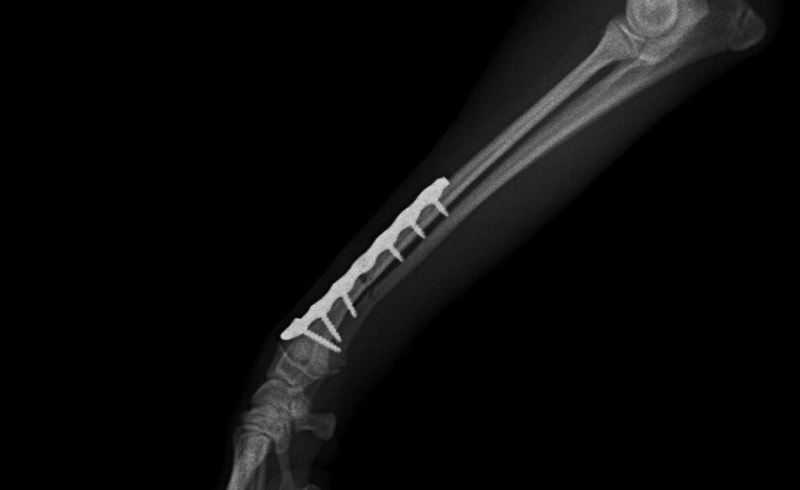

橈尺骨骨折 : 症例1 | 症例2 | 症例3 | 症例4 | 症例5 | 症例6 | 症例7

: 症例8 | 症例9 | 症例10 | 症例11 | 症例12 | 症例13 | 症例14

: 症例15 | 症例16 | 症例17 | 症例18 | 症例19 | 症例20 | 症例21

トイプードル 右遠位橈尺骨短斜骨折のALPSによる内固定